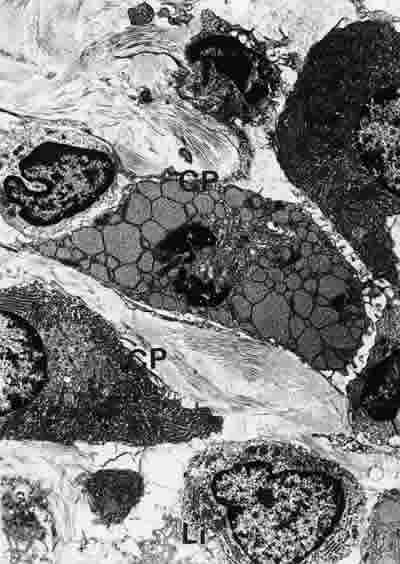

Figura 28

BIOPSIA EN UN PACIENTE CON SS1-GRADO I. SE OBSERVAN CÉLULAS PLASMÁTICAS (CP) CON GRANDES CISTERNAS DE REr MUY ELECTRODENSAS Y LINFOCITOS (Li) CON ABUNDANTES ORGÁNULOS SUBCELULARES. EL TEJIDO ES LAXO. MICROSCOPIA ELECTRÓNICA. MAGNIFICACIÓN ORIGINAL X3000.